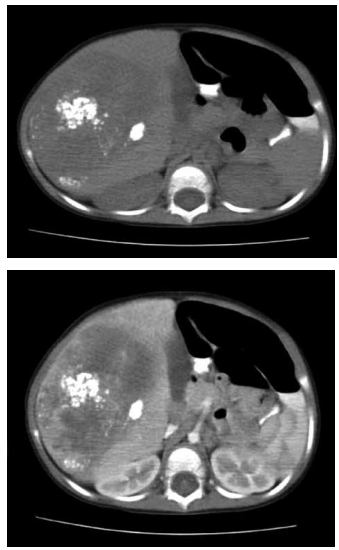

Criança, 18 meses, apresentando massa indolor

palpável no quadrante superior direito do abdome e perda de peso. Solicitados exames laboratoriais demonstrando anemia e elevação de alfafetoproteina (AFP) e

exame de imagem conforme demonstrado abaixo.